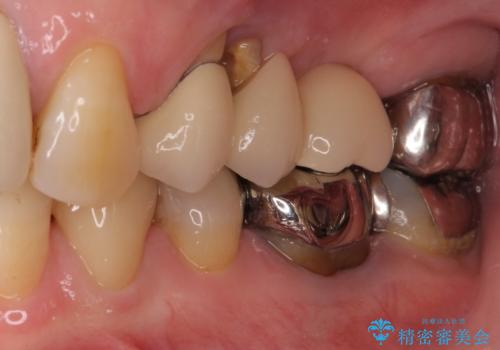

ブリッジの土台が割れて痛い インプラントによる補綴治療

- 上の奥歯に装着されているブリッジが痛むとのことで来院された患者様です。

診察した結果、ブリッジの土台となっている歯が割れていたため、抜歯が必要となりました。

欠損している歯数が多いため、ブリッジによる補綴治療は困難と判断し、インプラントによる補綴治療を行うこととしました。

インプラントを埋入するために必要な骨の高さがなかったため、上顎洞底の粘膜を挙上しました。

手術後は処置部に痣や腫脹が出現したり、痛みが出たりしましたが、補綴治療後は咬み合わせが安定し、大変満足していただきました。